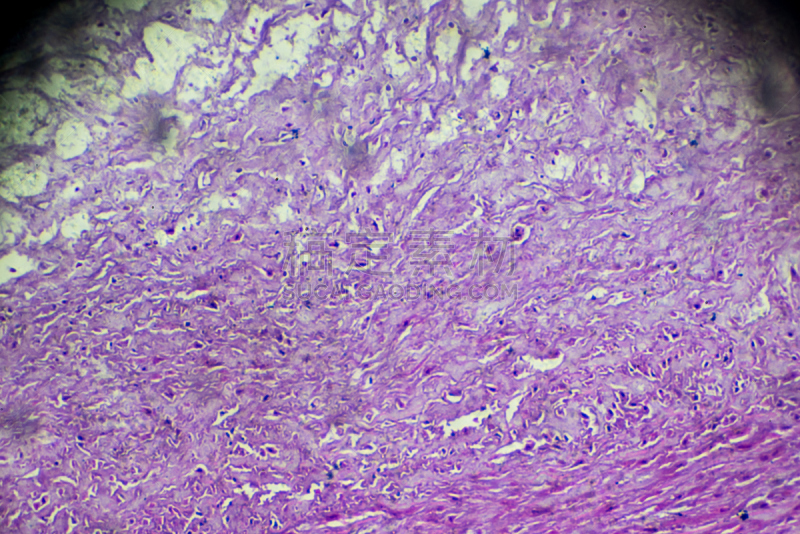

动脉粥样硬化详情

动脉粥样硬化,温和详情